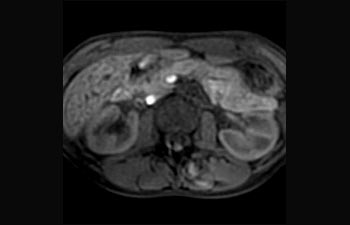

Leber und Pankreas